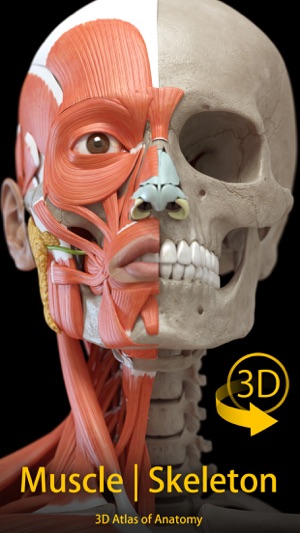

"Muscle | Skeleton - 3D Atlas of Anatomy" is a next generation anatomy atlas in 3D which gives you availability of interactive highly detailed anatomical models!

HIGHLY DETAILED ANATOMICAL 3D MODELS

• Skeletal System

• Muscular System

• Accurate 3D modeling

• Surfaces of the skeleton with high resolution textures up to 4K